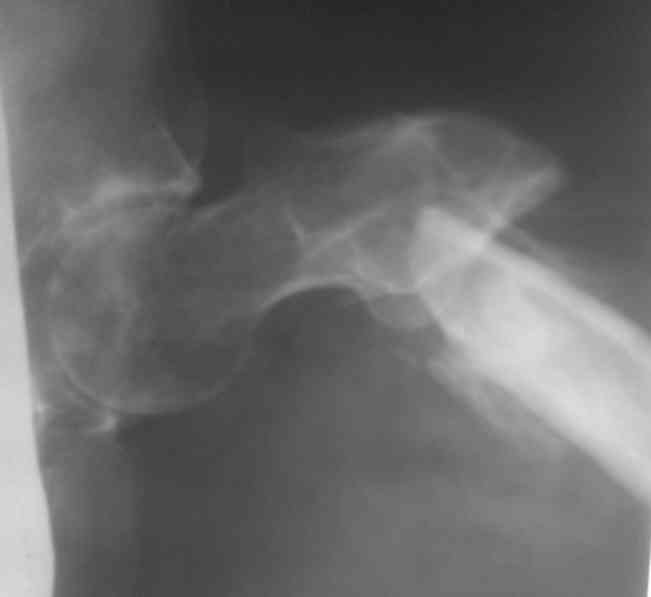

Re: Лечение ложного сустава шейки бедра

Название темы- это произвольно!! Второй снимок прилагаю!!!